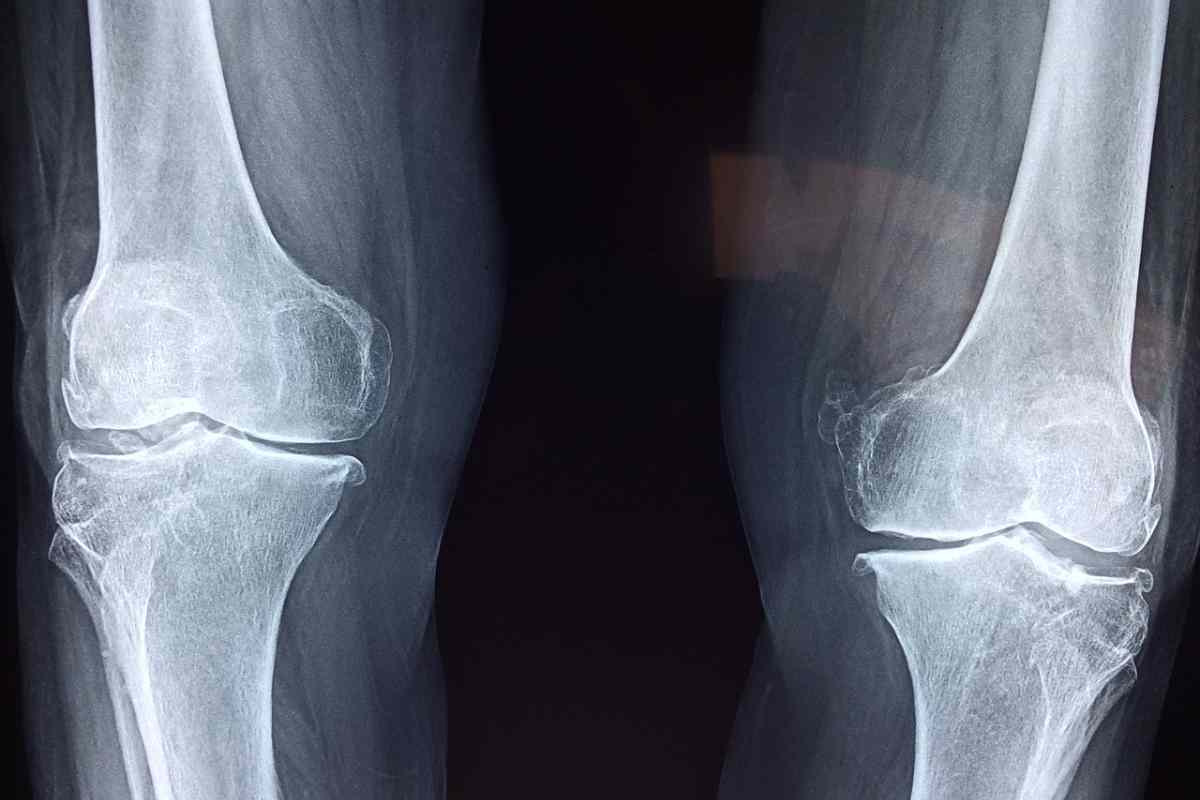

“L’infortunio al ginocchio destro – come si legge nel comunicato del suo team – è risultato essere peggiore del previsto. La risonanza magnetica ha evidenziato la rottura di un menisco, oltre a confermare la vecchia sospetta rottura del legamento crociato”.

Cavallo si opererà sia al ginocchio destro che a quello sinistro: “In accordo con il Team – sottolinea il Boano Factory – ha deciso di sospendere l’attività e di sistemare entrambe le ginocchia visto che anche il sinistro ha dei problemi. Auguriamo il meglio a Matteo e di tornare il prima possibile, noi saremo qua ad aspettarti! News sull’eventuale sostituto di Matteo arriveranno a breve”.